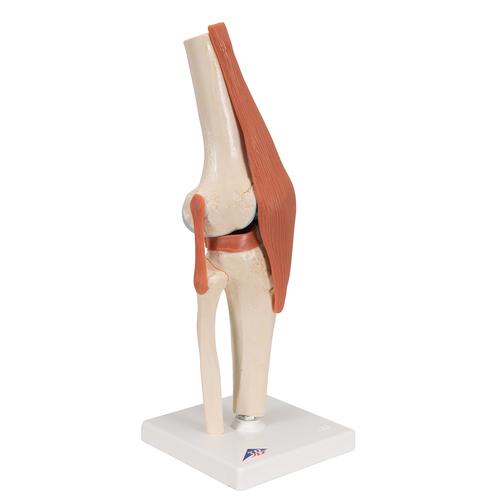

free3d.comAnatomical Medical Knee Joint With Ligaments Model, Life-size, For

free3d.comAnatomical Medical Knee Joint With Ligaments Model, Life-size, For

Deluxe Functional Knee Joint Model | Anatomical Models | Human Joint Models

www.3bscientific.comKnee Joint Models

www.3bscientific.comKnee Joint Models

Model – Knee Joint Model A82 | Access Health

mavink.comKnee Model

mavink.comKnee Model